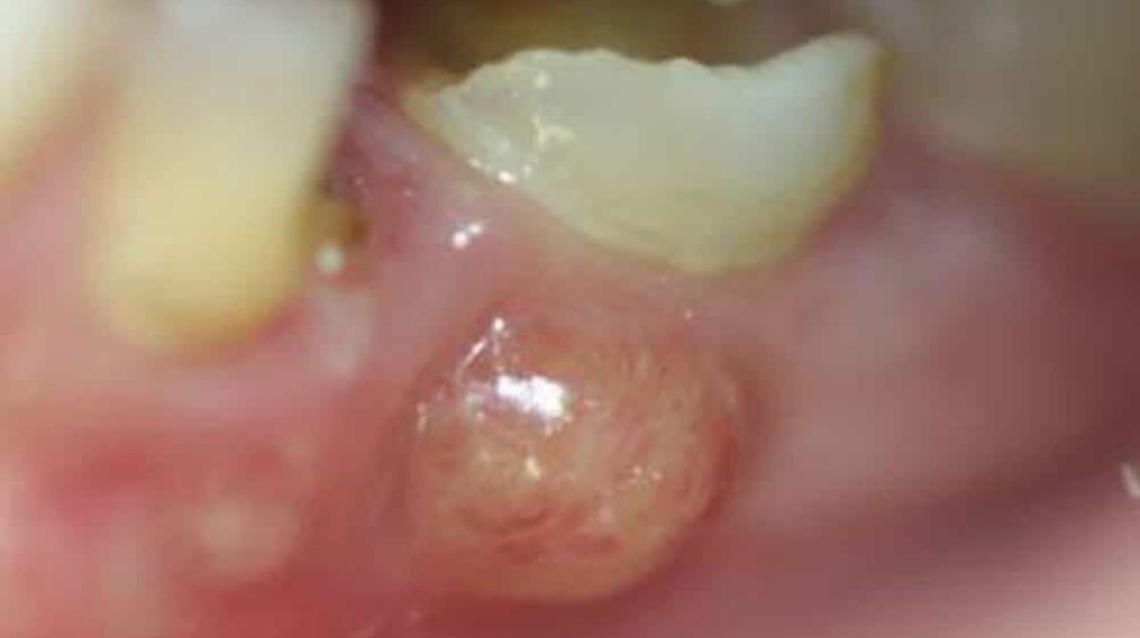

Parulis Fistula Dental Abscess Treatment And Symptoms Maiden Lane